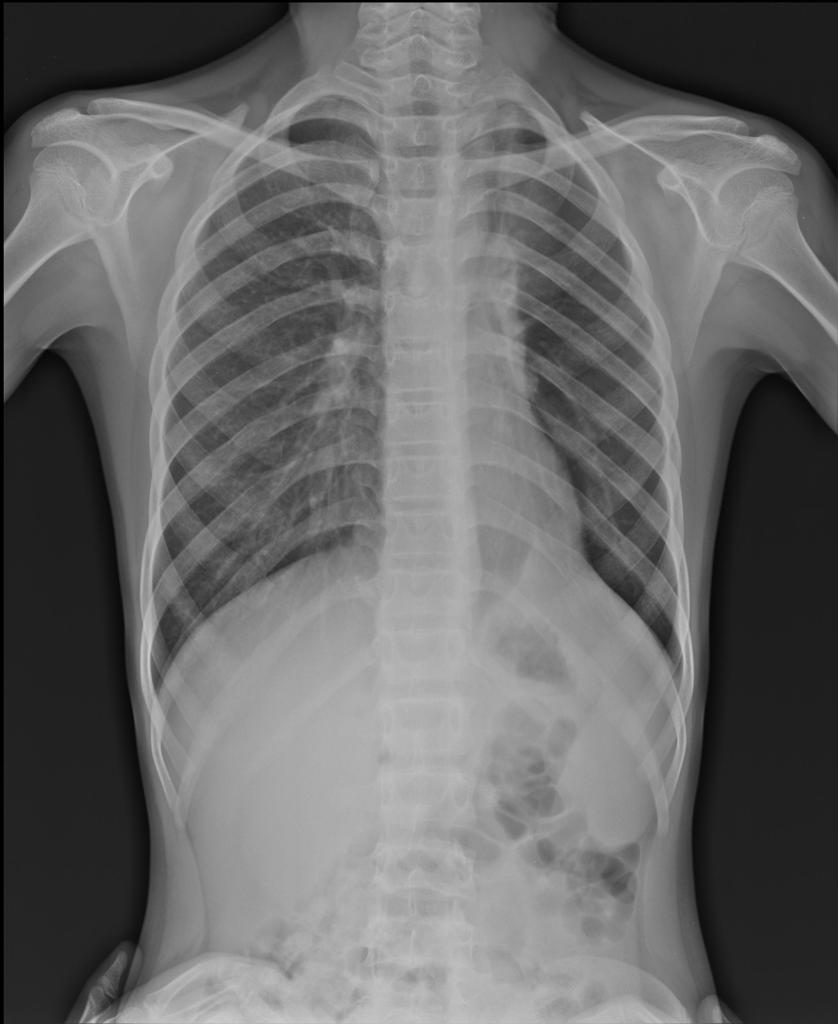

Рентген при гидротораксе

По рентгену невозможно установить характер жидкости в плевральной полости (воспалительный экссудат, гной, кровь, транссудат при сердечной недостаточности и т. д.), так как различное содержимое обуславливает одну и ту же рентгенологическую картину.

Затемнение на рентгене при гидротораксе обычно занимает не все легочное поле, а его нижний и средний отделы, а также область реберно-диафрагмального синуса.

Остается «свободной» небольшая верхняя часть легочного поля (субтотальный гидроторакс). При большом количестве содержимого легочное поле оказывается затемненным полностью (тотальный гидроторакс), при этом иногда определяется «плевральное окно» — участок просветления во внутренней зоне верхних отделов легочного поля.

При гидротораксе рентген имеет интенсивное, однородное затемнение, на его фоне обычно не определяются (или плохо различимы) элементы легочного рисунка и корень легкого, оно перекрывает тень сердца и сливается с ней (при левостороннем расположении). Плохо дифференцируется (или вообще становится неразличим) купол диафрагмы на стороне гидроторакса.

Верхняя граница затемнения дугообразная, «выгнутая» книзу, она направлена от наружного отдела легочного поля вниз и к срединной тени, эта граница может быть не совсем четкой. Прозрачность легкого на участке сразу выше этой границы обычно снижена за счет сдавления легкого содержимым в плевральной полости или за счет патологических изменений в самом легком, например, при пневмонии. Если количество жидкости велико, то легочное поле затенено на всем протяжении (тотальный гидроторакс) и верхняя граница содержимого в плевральной полости не определяется.

Важным признаком плеврального выпота на рентгене при гидротораксе является смещение тени средостения в противоположную от патологии сторону. Такое смещение проще выявить, ориентируясь на смещение трахеи, также определяется соответствующее смещение сердечной тени (при этом должна быть симметричной установка обследуемого — необходимо оценить положение грудинных концов ключиц, они находятся на примерно одинаковом расстоянии от остистых отростков грудных позвонков). При гидротораксе смещение тени средостения на рентгенограмме не всегда выражено в связи с тем, что легкое на стороне поражения «поджимается» (компремируется) содержимым в плевральной полости (образуется так называемый компрессионный ателектаз легкого). Также гидроторакс может сочетаться с ателектазом легкого на стороне поражения в результате обтурации бронха (например, опухолью).